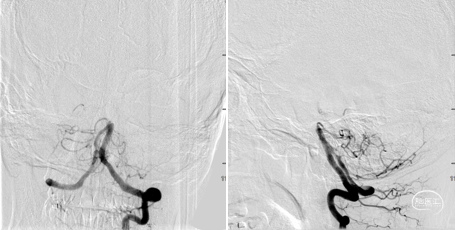

6F导引导管,拟取栓后处理狭窄,必要时支架成型。

通过相对容易,考虑尖有代偿,远段有返流,微导管位置未放置过高。

微导管造影。